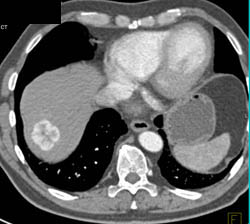

Occlusion of Hepatic Artery S/P Transplant With Liver Infarction